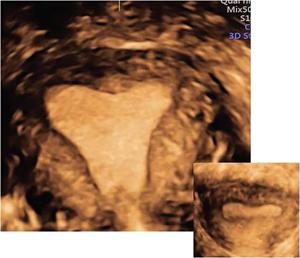

MÜLLERIAN DUCT ANOMALIES Rajani Gorantla Müllerian ducts are a pair of tubular structures that give rise to uterus, cervix, fallopian tubes and upper two-thirds of vagina. Disruption or failure of normal development can result in occurrence of Müllerian duct anomalies (MDAs). These are commonly associated with other congenital anomalies of urinary tract and ovaries due to the close relationship between the development of mesonephric and paramesonephric ducts; few patients also have associated skeletal system anomalies. The prevalence of MDAs in an unselected population was 5.5%; 8% among the infertile women, 12.3% in women with a history of recurrent pregnancy loss and 24.5% in women with miscarriage and infertility. Most of the patients with MDAs are asymptomatic and found incidentally on imaging for any other gynaecological problems, in evaluation of a patient with renal, skeletal or abdominal wall abnormalities. In symptomatic women, complains are related to the type, severity, obstructive anomaly or nonobstructive anomaly. The symptoms can be obstetric or gynaecological related, includes recurrent spontaneous abortions, infertility, preterm labour, intrauterine growth restriction and abnormal foetal lie. Few adolescent girls may present with primary amenorrhoea, hypomenorrhoea, abnormal vaginal bleeding, cyclical pain and mass. Rarely they can present with pelvic inflammatory disease with abnormal vaginal discharge, dyspareunia and urinary tract infections. The female reproductive system develops from a pair of Müllerian or paramesonephric ducts, urogenital sinus and vaginal plate. The ovaries develop separately from the primordial ridge. It is of great importance to understand the normal stages of development, as failure or interruption of any of these stages can lead to a simple to complex spectrum of anomalies. The three stages of Müllerian duct development include: At 6–10 weeks of gestation age, two paired Müllerian ducts and Wolffian ducts formation occurs. When Y chromosome factor (testicular determining factor) is absent, the Wolffian ducts undergo degeneration. The Müllerian ducts further elongate caudally and cross the Wolffian ducts to fuse in the midline. At 10–13 weeks of gestation age, caudal and lateral fusion of the two Müllerian ducts forms primitive uterovaginal canal, which is possessed of solid tissue initially located side by side and further internal canalization leads to the formation of two channels/canals divided by a septum. At this stage, there is reabsorption of the caudal septum and forms single cervical canal and vagina lumen. In around 15–20 weeks of gestation age, complete resorption of the septum takes place in a caudocranial direction from the isthmus to fundus and development of single endometrial cavity results. The fused caudal part of Müllerian ducts gives rise to the uterus, cervix and upper two-thirds of vagina; the unfused cranial part forms the fallopian tubes (Fig. 11.14.1.1). The lower vagina develops from the urogenital sinus, which is separated from the rectum by urorectal septum around 7 weeks of gestation age. The primitive uterovaginal canal embeds into the dorsal wall of urogenital sinus and forms Muller’s tubercle. Around 13 weeks of gestation, two solid masses known as sinovaginal bulbs originate from the upper part of the Muller’s tubercle, further proliferate into the caudal end of the uterovaginal canal to become a solid vaginal plate. Later canalization or degeneration of the central cells of the vaginal plate forms the lower vagina, which is usually completed by 20 weeks’ gestation. The vertical fusion of the upper and lower vagina occurs with resorption of tissue in between and forms single vaginal cavity (Fig. 11.14.1.2). The vaginal lumen is separated from the urogenital sinus by the hymenal membrane. Just before birth, the hymen normally ruptures due to retrogression of the central epithelial cells. However, a thin fold of mucous membrane persists around the vaginal introitus. The ovaries develop separately from migration of primordial germ cells to the genital ridge. Ureteric buds develop separately and concurrently. So renal anomalies are most commonly associated with MDAs with an association of 30%–50%. Various classification systems have been proposed over the past several decades to describe MDAs. Ideally, same classification system needs to be followed by a gynaecologist, surgeon and radiologist for better communication. Buttram and Gibbons classification was suggested in 1979, and it was based upon the level of failure in normal development and segregate the anomalies into groups with similar clinical manifestations, treatment, and prognosis for foetal salvage. According to Buttram and Gibbons, the uterine anomalies were classified into six classes as described in Table 11.14.1.1. The drawback is the lack of classification of vaginal and other anomalies separately. The ASRM (previously the American Fertility Society – AFS) classification system is the most widely accepted classification worldwide over the past years and was introduced in 1988. According to this classification, MDAs are classified into seven classes (class I to class VII) as mentioned in Table 11.14.1.2. However, several limitations have been described by Grimbizis and Campo in 2010 (Fig. 11.14.1.3). The drawbacks of the ASRM classification system are as follows: Hence in 2016, an updated classification of uterine septum, that is ASRM-2016 was proposed and officially approved morphometric criteria are given for distinguishing between septate, normal/arcuate and bicornuate uteri (Table 11.14.1.3). The VCUAM classification was proposed in the year 2005. The main concern is to provide a simple, systematic, clinical classification in addition to providing a precise reflection of the entire malformation. The female genital organs were divided into the following subgroups in accordance with the anatomy: vagina (V), cervix (C), uterus (U) and adnexa (A). Associated malformations were assigned to a subgroup (M) relative to each specific organ. The disadvantage is due to its inherent complexity, and more than 56,700 individual combinations of anomalies are possible. ESHRE and ESGE established a common working group named CONgenital UTerine Anomalies (CONUTA) in order to devise an improved classification system (Table 11.14.1.4). It was published in 2013. Anatomy is the basis for systemic categorization of the MDAs. The subclasses are divided by the different degrees of uterine deformity and their clinical significance (Fig. 11.14.1.4). Cervical and vaginal anomalies are classified into independent supplementary subclasses (Figs. 11.14.1.5–11.14.1.6). For most of the clinicians, it helped as starting point for the development of guidelines for their diagnosis and treatment. The malformations are graded according to severity, U0–U5, C0–C4 and V0–V4, with U5, C4 and V4 being more severe. Class U3 incorporates bicorporeal fusion defects (didelphys and bicornuate) as this was considered as a more functional mode of classification. Arcuate uterus was not included separately, but this is categorized under normal variant into class U1c. Recent studies have demonstrated that the ESHRE/ESGE system provides an effective and comprehensive classification for almost all the currently known MDAs and overcomes the limits of previous classifications. However, there is a relative overdiagnosis of septate uterus with the application of ESHRE–ESGE criteria has been reported and which potentially might lead to unnecessary surgical overtreatment. C0 C1 C2 Normal cervix Septate cervix Double ‘normal’ cervix C3 C4 Unilateral cervical aplasia Cervical aplasia U4 V0 V1 V2 V3 Normal vagina Longitudinal nonobstructing vaginal septum Longitudinal obstructing vaginal septum Transverse vaginal septum and/or imperforate hymen V4 Vaginal aplasia C MDAs’ characterization and classification is of great significance, as the treatment is determined by the type and severity of abnormality. The various imaging modalities available include: HSG was the most recognized imaging modality, earlier to the development of the ultrasonography (USG) and MRI. It is an invasive fluoroscopic-guided procedure for uterine and tubal assessment, and is performed during the midproliferative phase of the cycle, ideally between days 7 and 10 of the cycle when endometrium is thin. Fluoroscopic spot images obtained to evaluate uterine configuration, uterine filling defects and fallopian tube patency. HSG allows evaluation of only the component of the uterine cavity that communicates with the cervix. The anatomic information about myometrium and external fundal contour will not be provided by HSG. The diagnostic criteria used to diagnose MDAs on HSG include: HSG findings of different MDAs are described in Table 11.14.1.5 and Fig. 11.14.1.10. Virtual HSG is a noninvasive technique performed by using a computed tomography (CT) scanner, done 45 s after the contrast material instillation begins. Contraindications are similar to those for HSG and include pregnancy and active pelvic infection. There is no necessity for retraction of the uterus or manipulation of the cervix. The procedure is quick, easy and prophylactic administration of antibiotics is not required. The use of a power injector helps to ensure a steady low pressure of instillation. The procedure is less painful, more comfortable and easily tolerated by patients than conventional HSG. Radiation exposure sometimes requires cervical clamping, which may result in complications such as bleeding and infection. Transabdominal pelvic ultrasound can diagnose uterine anomalies with accuracy rate of 47%. Two-dimensional transvaginal ultrasound (TVUS) has high sensitivity and specificity than transabdominal study and provided some information about external and internal fundal contours. The detection rate is high if the scan is performed in secretory phase due to better visualization of endometrium. Three-dimensional USG shows great accuracy than 2D USG in evaluation of the uterine morphology. The technique of 3D USG varies with different vendors. It displays both the external and internal fundal contours and lower uterine segment by acquisition of single coronal view of uterus (c-view) (Fig. 11.14.1.11). The only disadvantage is that it is transvaginal study and shall not be done in paediatric age group and sexually inactive women. Three-dimensional TVUS has become the first line of screening tool in most of the infertility clinics as it is noninvasive, faster, repeatable, allows storage of volume data and has multiplanar capability for systematic evaluation of the uterine and cervical cavities. The salient features of various Müllerian anomalies on 3D USG are described in Table 11.14.1.6 with images. Three-dimensional ultrasound is combined with sonosalpingography in this technique and provides better delineation of the uterine morphology. It is a less invasive procedure done in proliferative phase with instillation of saline into the uterine cavity and assessment of the uterus will be done. MRI is a universally accepted imaging modality in the documentation of MDAs and accuracy rate of 100% have been reported. MRI provides excellent delineation of both the internal and external uterine anatomies. T2-weighted (T2W) images are the mainstay of pelvic imaging and are performed without fat suppression. T1-weighted (T1W) images are mainly for the haemorrhagic content. The disadvantages of MRI include time-consuming procedure, not cost-effective, large body habitus, pacemakers, recent surgical history and claustrophobia. The current and proposed MRI protocol given by the European Society of Urology (ESUR-MRI protocol) intends a dedicated evaluation of MDAs as mentioned below (Fig. 11.14.1.12): Vaginal anomalies can be accurately diagnosed with the prior administration of the ultrasound gel, to distend vagina (Fig. 11.14.1.13). It will help in better diagnosis of complex vaginal anomalies, like vaginal septations or vaginal duplication. The normal MRI appearance of uterocervical canal and vagina are shown in Fig. 11.14.1.14. Uterine aplasia/hypoplasia/agenesis is class 1 MDA according to ASRM classification and U5 uterine anomaly according to ESHRE classification. It is a formation defect of the paramesonephric ducts with complete or segmental agenesis of uterus and vagina. The incidence rate is around 10%–15% of all MDAs and considered as the most severe form of uterine anomaly. Most of them have complete uterovaginal agenesis with no single completely developed uterine cavity and are associated with Mayer–Rokitansky–Küster–Hauser syndrome (MRKHS). Two types of this syndrome are depicted. The typical form or type A represents the absence or remnants of the uterus, cervix, upper two-thirds of vagina with normal ovaries and fallopian tube (Fig. 11.14.1.15). The atypical form or type B is associated with the abnormalities of the ovaries, fallopian tubes and genitourinary system (Fig. 11.14.1.16). In a few cases (approximately 10%), unilateral or bilateral uterine remnants and with or without endometrial cavity will be seen (Fig. 11.14.1.17). Most of them present with primary amenorrhoea due to complete uterovaginal agenesis and manifest as MRKHS. These patients have normal secondary sexual characteristics due to the preserved normal ovarian function and phenotype. If uterine remnants with functional cavity is present, will present with cyclical pain along with amenorrhoea due to cryptomenorrhoea and haematometra. USG is the first modality for identification of these anomalies, absence of uterus with normal ovaries is diagnostic. But, it is difficult to locate the uterine remnants and cavity due to small acoustic window. MRI is the gold standard and it classifies into uterovaginal agenesis and hypoplasia. If hypoplasia is identified, sagittal and axial sections are taken. These remnants are seen as T2 hypointense tubular structures, located in close relation to ovaries in the adnexa. Once we identify the uterine remnants, it is important to look for the functional endometrial cavity. These will have reduced endometrial and myometrial width. MRI can easily delineate the zonal anatomy due to its high soft tissue contrast resolution. The management of Müllerian agenesis consists of counselling for the patient and her parents. Some patients with MRKHS opt for creation of neovagina for normal sexual life. Various techniques are available. In the presence of a functional Müllerian remnant, regardless of whether it is communicating or not, medical suppression of menses can be initiated and should be followed by laparoscopic removal of the hypoplastic remnant. Unicornuate uterus or hemiuterus is defined as the unilateral uterine development and the contralateral Müllerian duct could be either partially formed or absent. It is a formation defect and the necessity to classify it in a different class than that of uterine agenesis, which is also a formation defect, is due to the existence of a fully developed functional uterine hemicavity. It is considered as class II anomaly according to ASRM classification and class U4 according to ESHRE classification. The frequency rate is around 20% of MDAs. Renal anomalies most often occur in association with unicornuate uterus and usually on the same side of uterine agenesis. Further unicornuate uterus is divided into two subclasses depending on the presence or absence of a functional rudimentary cavity in ESHRE classification: In ASRM classification, unicornuate uterus is divided into four subcategories: Mostly asymptomatic and presence of the noncommunicating uterine remnants will be identified at the time of infertility work up or caesarean section. If a functional cavity is present, the presentation is dysmenorrhoea or haematometra in an adolescent. The common obstetrics-related complications include abnormal foetal lie, intrauterine growth retardation, preterm delivery, placental abnormalities and uterine rupture. Gynaecological complications are ectopic pregnancy and endometriosis due to retrograde menstruation. On imaging, unicornuate uterus is seen as tubular and fusiform or banana-shaped structure at paramedian location, the endometrium is narrow and tapers to the apex with normal myometrial anatomy and reduced uterine volume. The rudimentary cavity or remnants are better depicted on 3D USG (Fig. 11.14.1.18) and MRI. However, MRI is superior to USG due to its high soft tissue resolution. The rudimentary cavity can communicate with main cavity or connected by fibrous band. The nonfunctioning cavity will be seen as T2 hypointense structure with loss of zonal anatomy (Figs 11.14.1.19 and 11.14.1.20), whereas the functioning cavity will show the deformed zonal anatomy (Fig. 11.14.1.21), and its complications like haematometra as T1/T2 hyperintense endometrial collection. Unicornuate uterus without rudimentary cavity does not require any procedure. But in the presence of communicating or noncommunicating rudimentary horn, surgical resection must be considered to prevent complications. Uterine didelphys is a class III MDA based on the ASRM classification and class U3b bicorporeal uterus according to ESHRE classification with an incidence rate of 5% among the uterine anomalies. It is a lateral fusion defect; results from complete failure of the Müllerian duct fusion. Two noncommunicating endometrial cavities with preserved zonal anatomy are seen with separate cervix. According to ESHRE classification, it is defined as external fundal indentation completely dividing the uterine corpus up to the level of external cervical os. It is most commonly associated with longitudinal vaginal septum in around 75% of cases. Some patients may show transverse vaginal septum and these will be obstructive or nonobstructive type. Renal anomalies are also commonly associated with uterine didelphys. Uterine didelphys is usually asymptomatic and diagnosed incidentally on pelvic examination or caesarean section. The uterine didelphys with obstructed vagina (Fig. 11.14.1.22) will present at adolescence as dysmenorrhoea, haematometrocolpos and haematosalpinx. Sometimes retrograde menstrual flow can cause endometriosis and pelvic adhesions. Obstetric-related complications include abortion/foetal growth restriction and poor pregnancy outcome. The uterine didelphys with obstructed hemivagina due to transverse vaginal septum and associated ipsilateral renal agenesis are the manifestations of the syndrome called obstructed hemivagina and ipsilateral renal agenesis anomaly/Herlyn–Werner–Wunderlich (HWW) syndrome (Fig. 11.14.1.23).